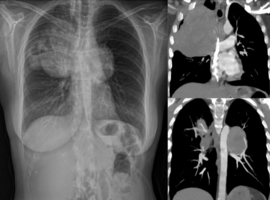

The Yule Log: Intrapulmonary Wooden Foreign Body Retained for Four Decades